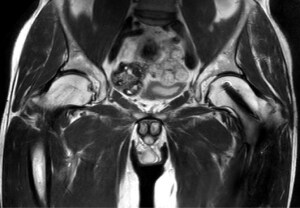

T2w TSE

Ingenia Ambition 1.5T